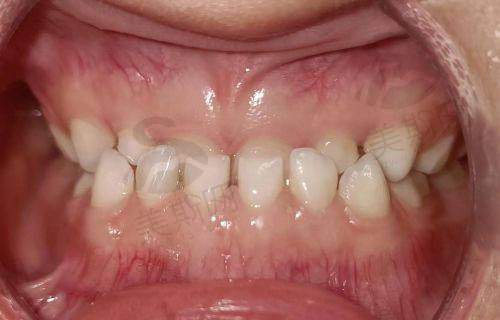

2. 牙齿矫正:提供传统金属托槽、自锁托槽、陶瓷半隐形、隐形矫正等多种方案,引进美国隐适美、时代天使等有名隐形矫正版牌,通过3D口扫技术提前预知矫正成效,满足不同年龄层患者的美观需求。